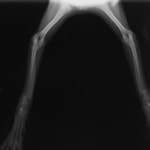

症例3:キルシュナーワイヤーのピンニングによる整復

ペルシャ猫 11ヶ月齢 雄

他院にて左大腿骨遠位の成長板骨折(salter-harrisⅠ型)が認められており、治療相談を目的として来院。当院にて、キルシュナーワイヤーを用いたピンニングにより骨折部位の整復を行いました。術後の経過は良好で、現在も経過観察中です。

術前レントゲン

術後レントゲン